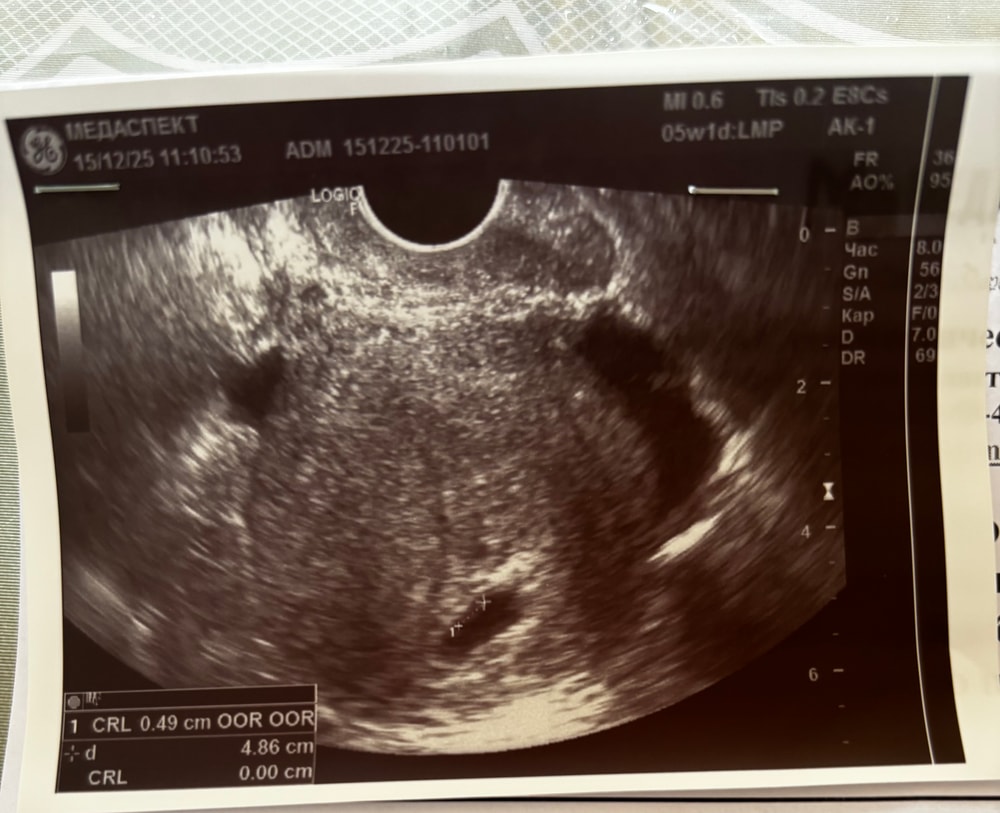

УЗИ 20 дпп

Результаты УЗИДевочки, посмотрите пожалуйста узи

жду ответа от ре, смущает форма пя, смотрели вагинальным датчиком

Я читала презентации по узи юеременных, что пя хоть и должно быть круглым, но овальной формы тоже считается нормой. Поэтому в плане формы всё в порядке. Или у вас переживания не с этим связаны?